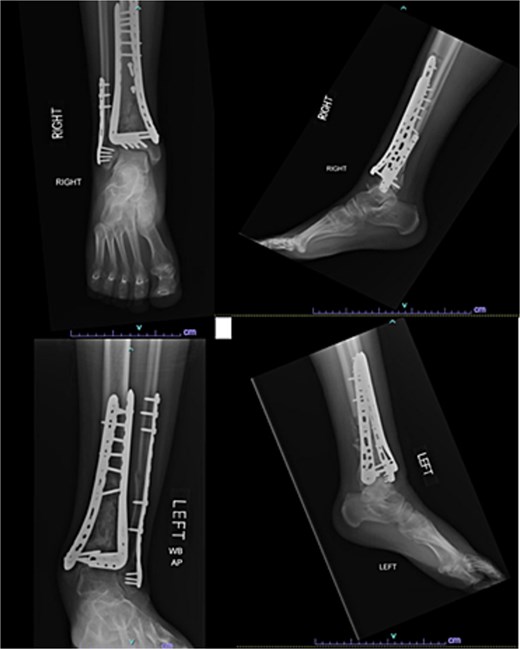

One year after the initial surgery, the left leg healed without any complications. However, the right leg developed nonunion through the distal tibia, along with posttraumatic arthritis. As a result, the patient underwent a right ankle fusion. Additionally, 2.5 years after the index surgery (1.5 years after the ankle fusion), the patient required removal of the right lateral fibular plate due to painful hardware. Six months later (3 years post-index surgery), the patient then underwent subtalar fusion due to post-traumatic arthropathy and ongoing pain (Fig. 2).

Radiographs of patient 1 obtained 3 years after the index procedure, including AP view of the left ankle and lateral and oblique views of the right ankle following subtalar fusion.

A 38-year-old male with a BMI of 27.5 kg/m2 and a history of alcohol use disorder, paranoid schizophrenia, smoking, and prior bilateral calcaneal fractures treated with ORIF 4 years earlier sustained bilateral pilon fractures after jumping from a third-story window (Fig. 3). He presented to the hospital 5 days after injury.

AP and oblique radiographs of patient 2 obtained after a fall, demonstrating bilateral pilon fractures and retained hardware from prior bilateral calcaneal ORIF.

Despite the patient’s noncompliance, he went on to heal uneventfully for the next 2 years until the patient fell from a height of 15 feet, resulting in a left bicondylar tibial plateau fracture and fracture of the left tibial shaft. These injuries required ORIF of his left tibia. Despite the new injury, the hardware from the pilon fractures was in proper alignment (Fig. 4).

Two-year follow-up AP and lateral radiographs of both ankles in patient 2 showing maintained alignment and hardware position.